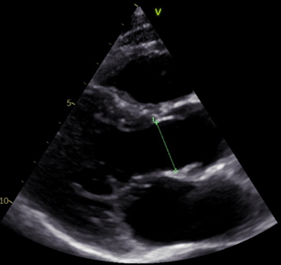

Most Foreshortened Example Least Foreshortened Example

The image on the left illustrates an example of the Most Foreshortened, while the Least Foreshortened example is shown on the right.